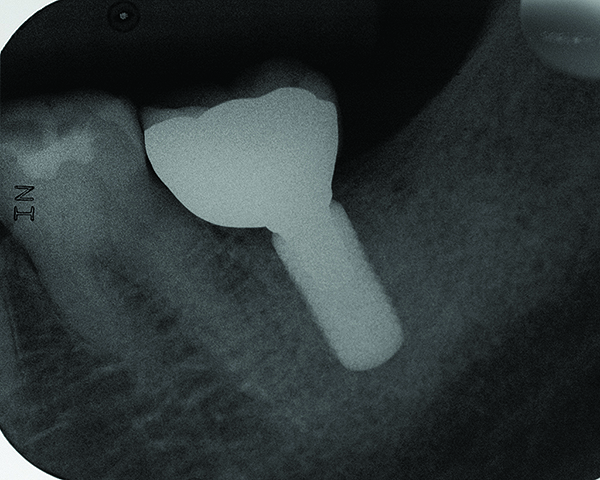

Fig 2. Radiograph of this same area. Note that there is no indication of bone loss and a long abutment collar. Hence, the diagnosis of peri-implant mucositis is given.

Figure 2